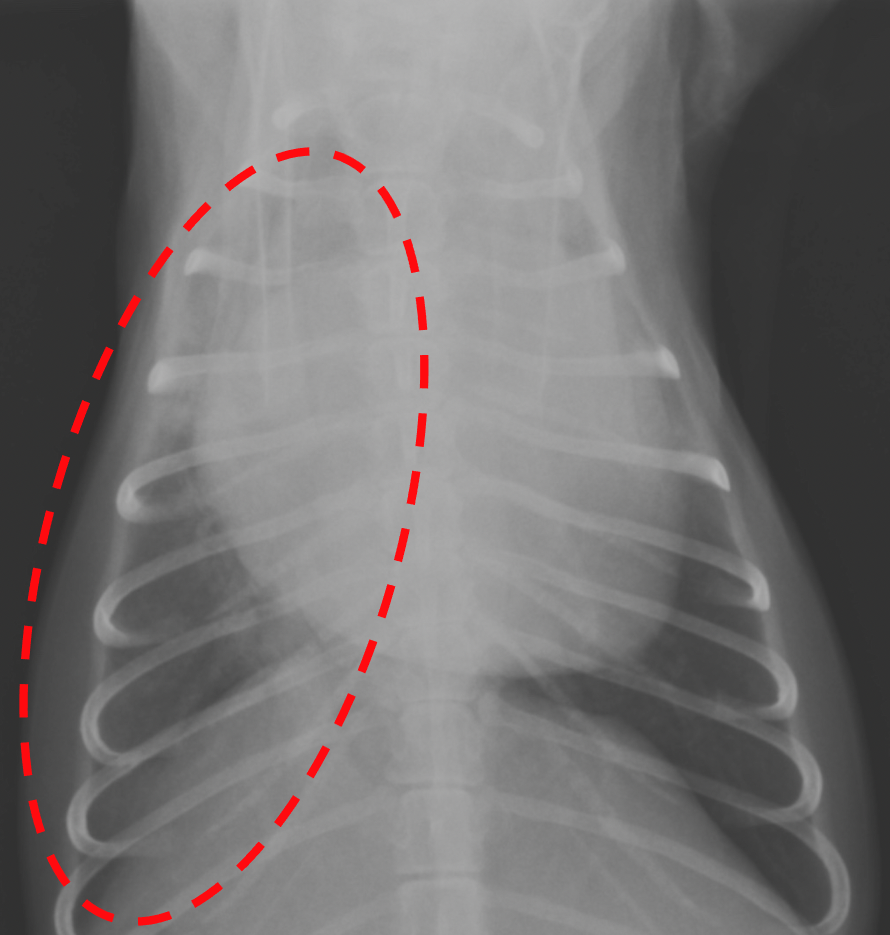

肺水腫が認められた領域(点線)が改善。